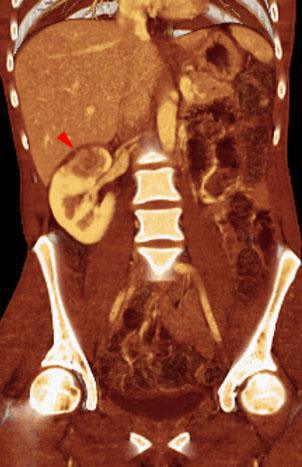

VR seccional. Visión coronal anterior. TC contrastado en fase venosa. Mujer de 39 años. Lesión hipodensa renal derecha con signos inflamatorios perirrenales (punta de flecha)